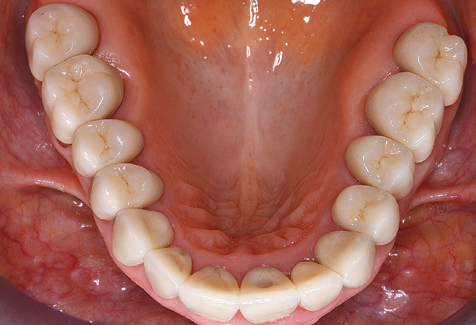

Due to the presence of periodontal disease, SPT was performed every three months in the first years following the insertion. The patient demonstrated a high degree of motivation and good compliance. The pocket depths recorded annually revealed a stable periodontal situation with a BOP index of below five per cent. On the basis of the stable periodontal situation and good cooperation on the patient’s part, the recall interval was extended to every six months as of the sixth year of the prosthetic function phase. Following the change in the recall interval, the respective annual documentation of the periodontal status continued to reveal a stable periodontal situation with no increase in the pocket depths and a BOP index below five per cent (Fig. 2a and b).

Fig. 2: The pocket depths recorded annually with six-monthly SPT display no increasing trend and a BOP index of below 5 per cent with a largely inflammation-free periodontal situation. a) PERIO status in 2011 (after five years with implants). b) PERIO status in 2016 (after ten years with implants).